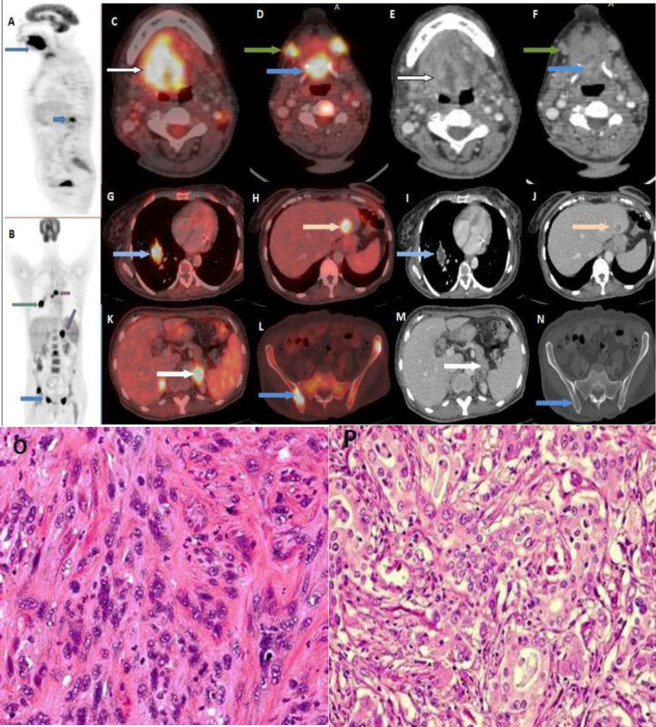

Results: On whole body 18F-FDG PET/CT, distant metastases were detected in 33 (11.7%) patients, all with locally advanced primary tumors corresponding to T category 3 and 4. Lung (6%) and bone (~6.7%) were the most common sites of distant metastasis. In nine patients metastases were detected below the diaphragm. Synchronous malignancies were discovered and histopathologically proven in 22 (7%) patients. Lung carcinoma was the most common synchronous tumor, detected in 9 patients. In seven patients synchronous tumour was detected outside the aerodigestive tract, of which four were below the diaphragm.

Conclusions: Of the distant metastasis diagnosed in 11.7% of HNC patients with TNM tumor category T3 and T4, 3% of metastasis lesions were detected below the diaphragm. Synchronous malignancy was diagnosed in 7% patients irrespective of primary HNC stage. These findings demonstrate the advantage of using whole body 18F-FDG PET/CT as an ideal and preferred modality for initial staging and screening of HNC patients since detection of distant metastasis or a synchronous malignancy changes the management approach in these patients.